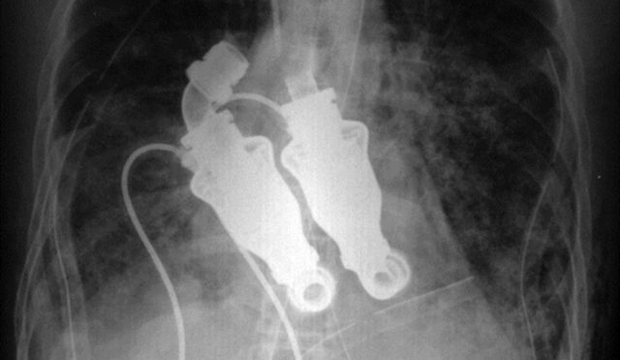

Доктор Билли Кон (Billy Cohn) и доктор Бад Фрейзер (Bud Frazier) удалили сердце Крейга, установив вместо него в грудную клетку данное устройство. Уже через день после операции пациент пришел в себя и сообщил своим спасителям, что замечательно себя чувствует.

Амилоидоз мистера Льюиса прогрессировал настолько быстро, что в марте 2011 года его лечащий врач сказал ему, что если не случится чудо, то он умрет через 12 часов. Поэтому с согласия жены мистера Льюиса, Линды, доктор Кон и доктор Фрейзер установили в его грудную клетку заменитель сердца, который был собран из деталей, большинство из которых были изготовлены в домашних условиях.

Устройство работает непрерывно, качая кровь при помощи специальных лопастей.